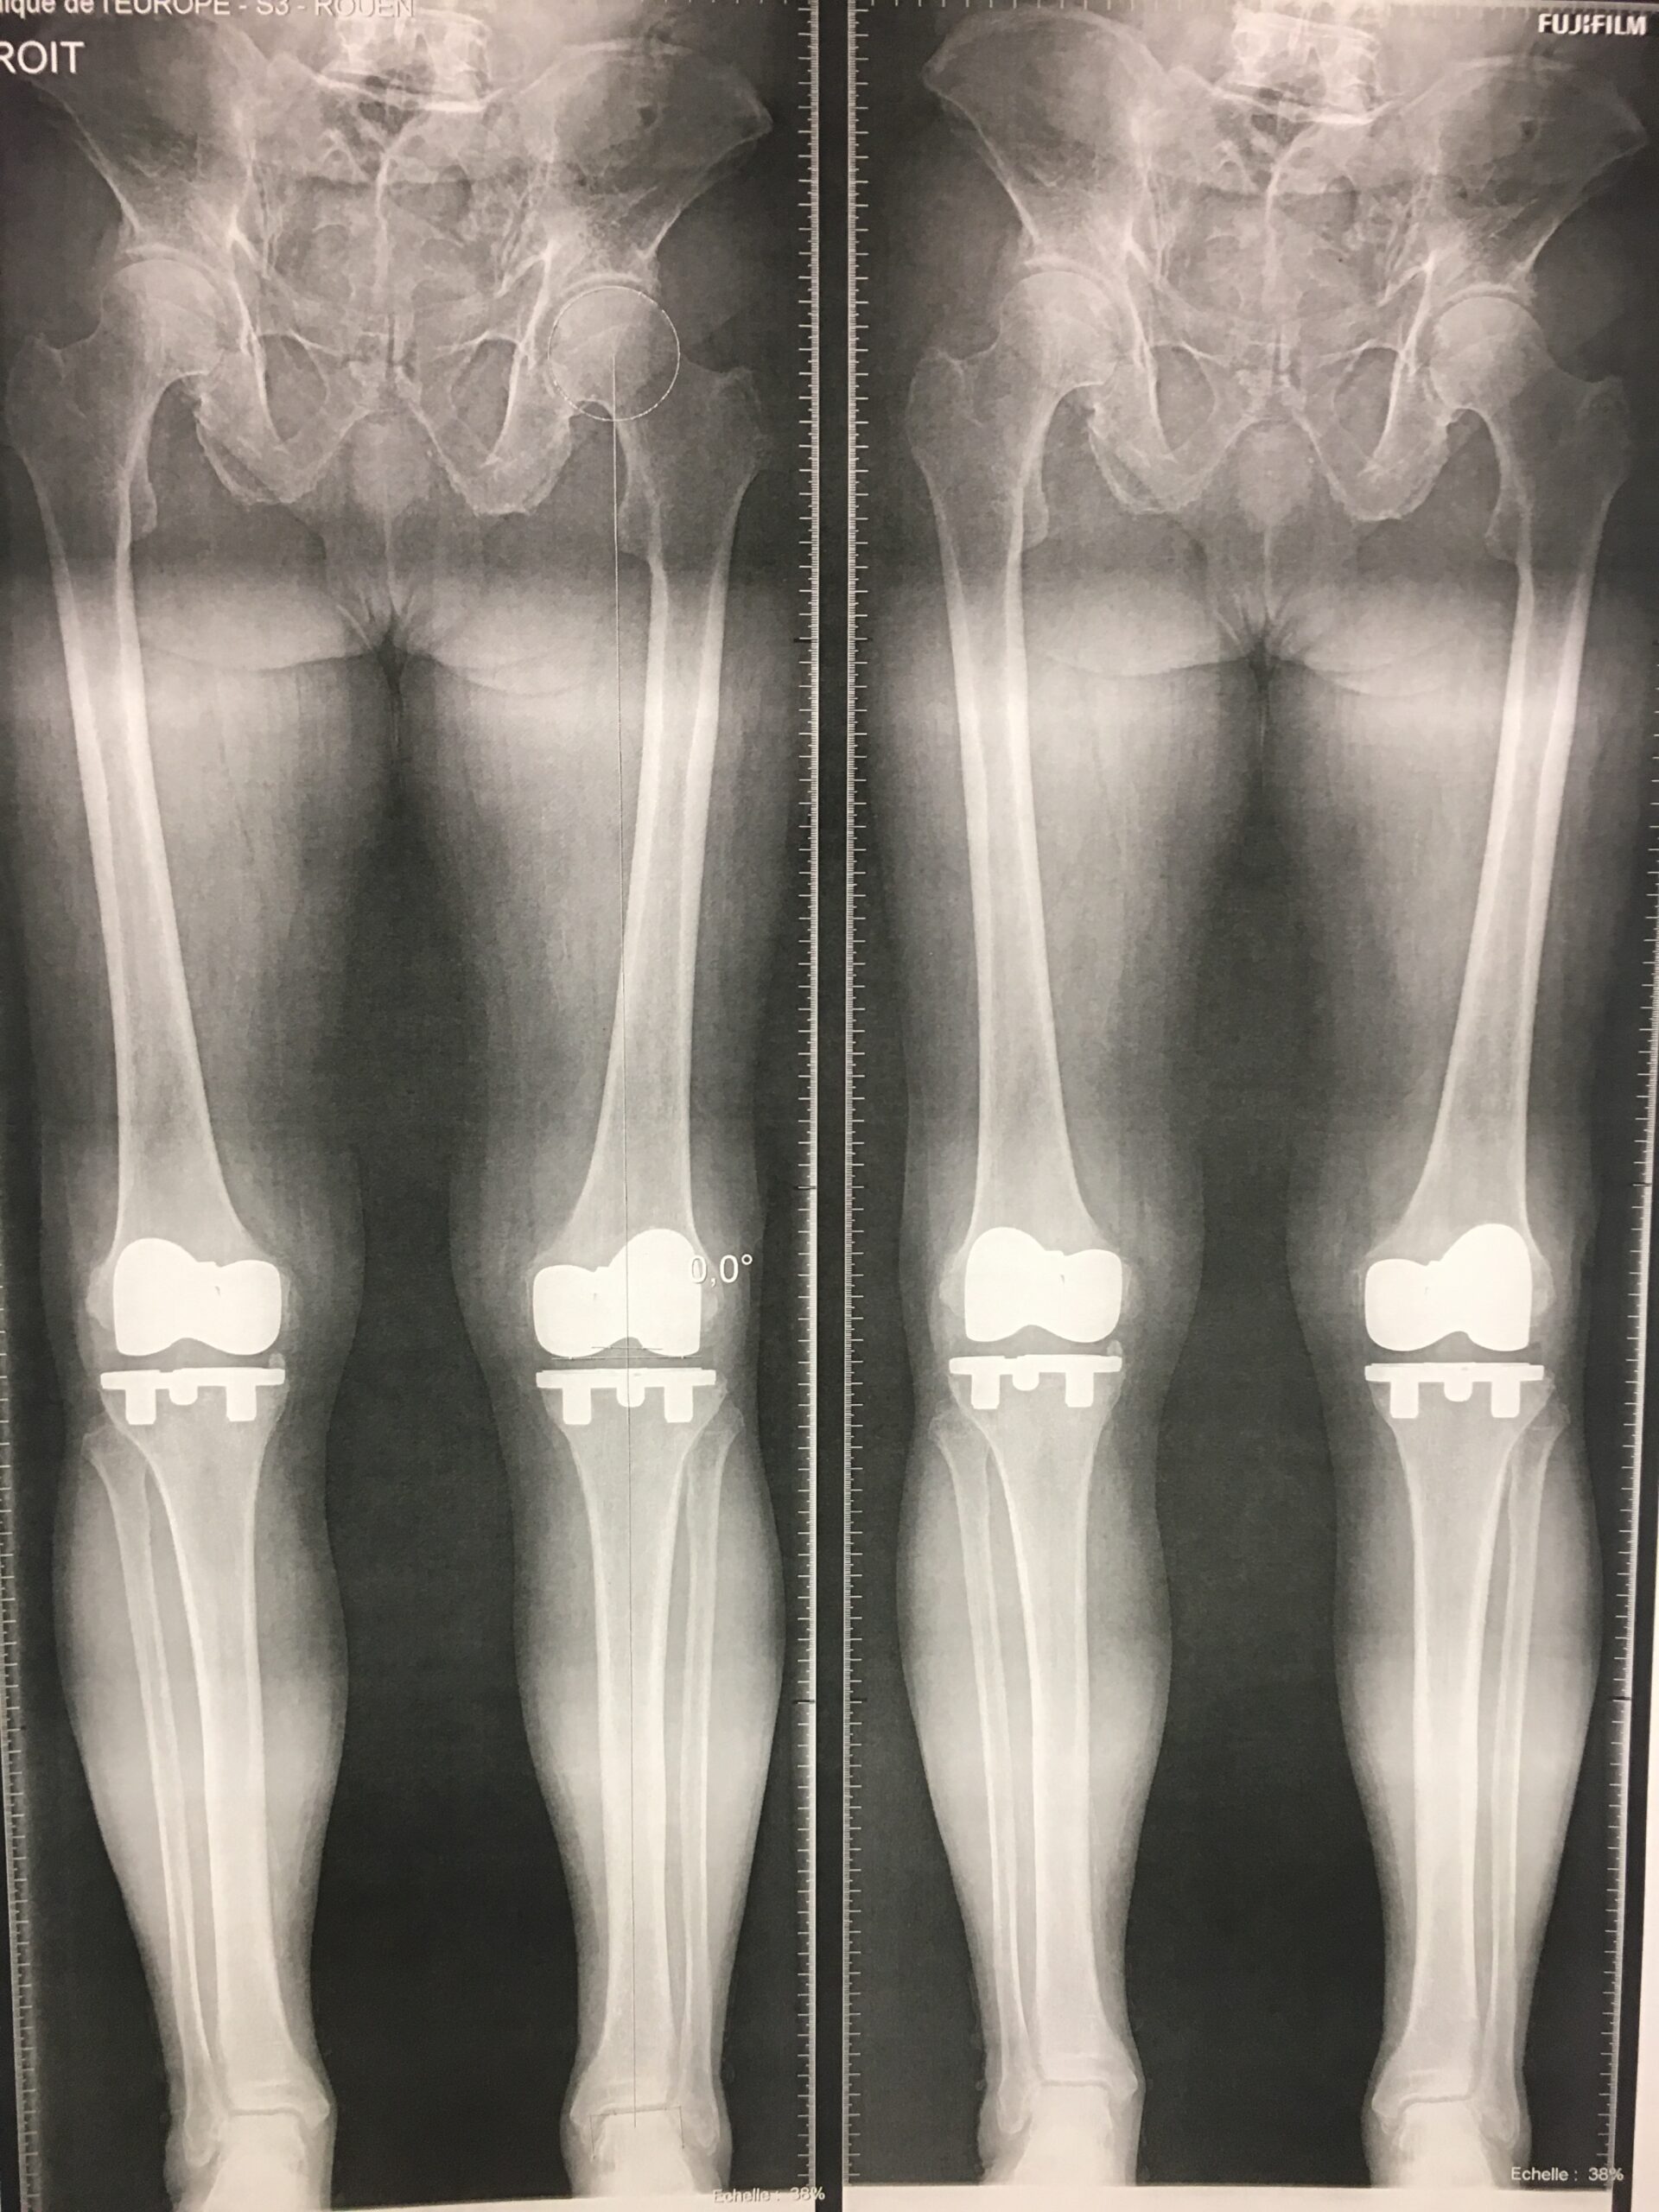

Spécialiste en chirurgie du genou et de la hanche.

Dr. Julien Synave est un chirurgien orthopédiste reconnu, spécialisé dans le traitement des pathologies complexes du genou, des articulations, ainsi que des membres inférieurs et supérieurs. Avec son expérience de plus de 30 ans, il vous proposera des solutions personnalisées pour soulager vos douleurs articulaires et améliorer votre mobilité.

J'ai été opéré d'une prothèse totale du genou droit le 29/2/2024 par le Dr Synave. J'ai beaucoup apprécié les explications, conseils et recommandations pré et post opératoires données par ce chirurgien. Je le recommande. Concernant la Clinique de l'Europe, de l'accueil le matin jusqu'à mon départ le soir (ambulatoire), tout a été parfait également.![]()